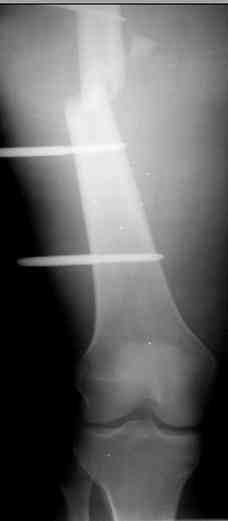

Больной 27 лет, мотоциклист. Поступил 23.04.10

ДЗ. О. перелом н.з левого бедра Gustillo 3b (c повредрение бедренной вены),

При поступлении Hb 66 ISS 40, фиксация стержневыми аппратами, сосудистые хирурги выполнили шов вены. Выполена резекция бедренной кости 9 см

Левое бедро пранируем продолжить фиксировать в стержневом аппрате.

Вопрос: что делать с левым бедром? Учитывая внутрисутавной характер перелома, дефект бедра 9 см.